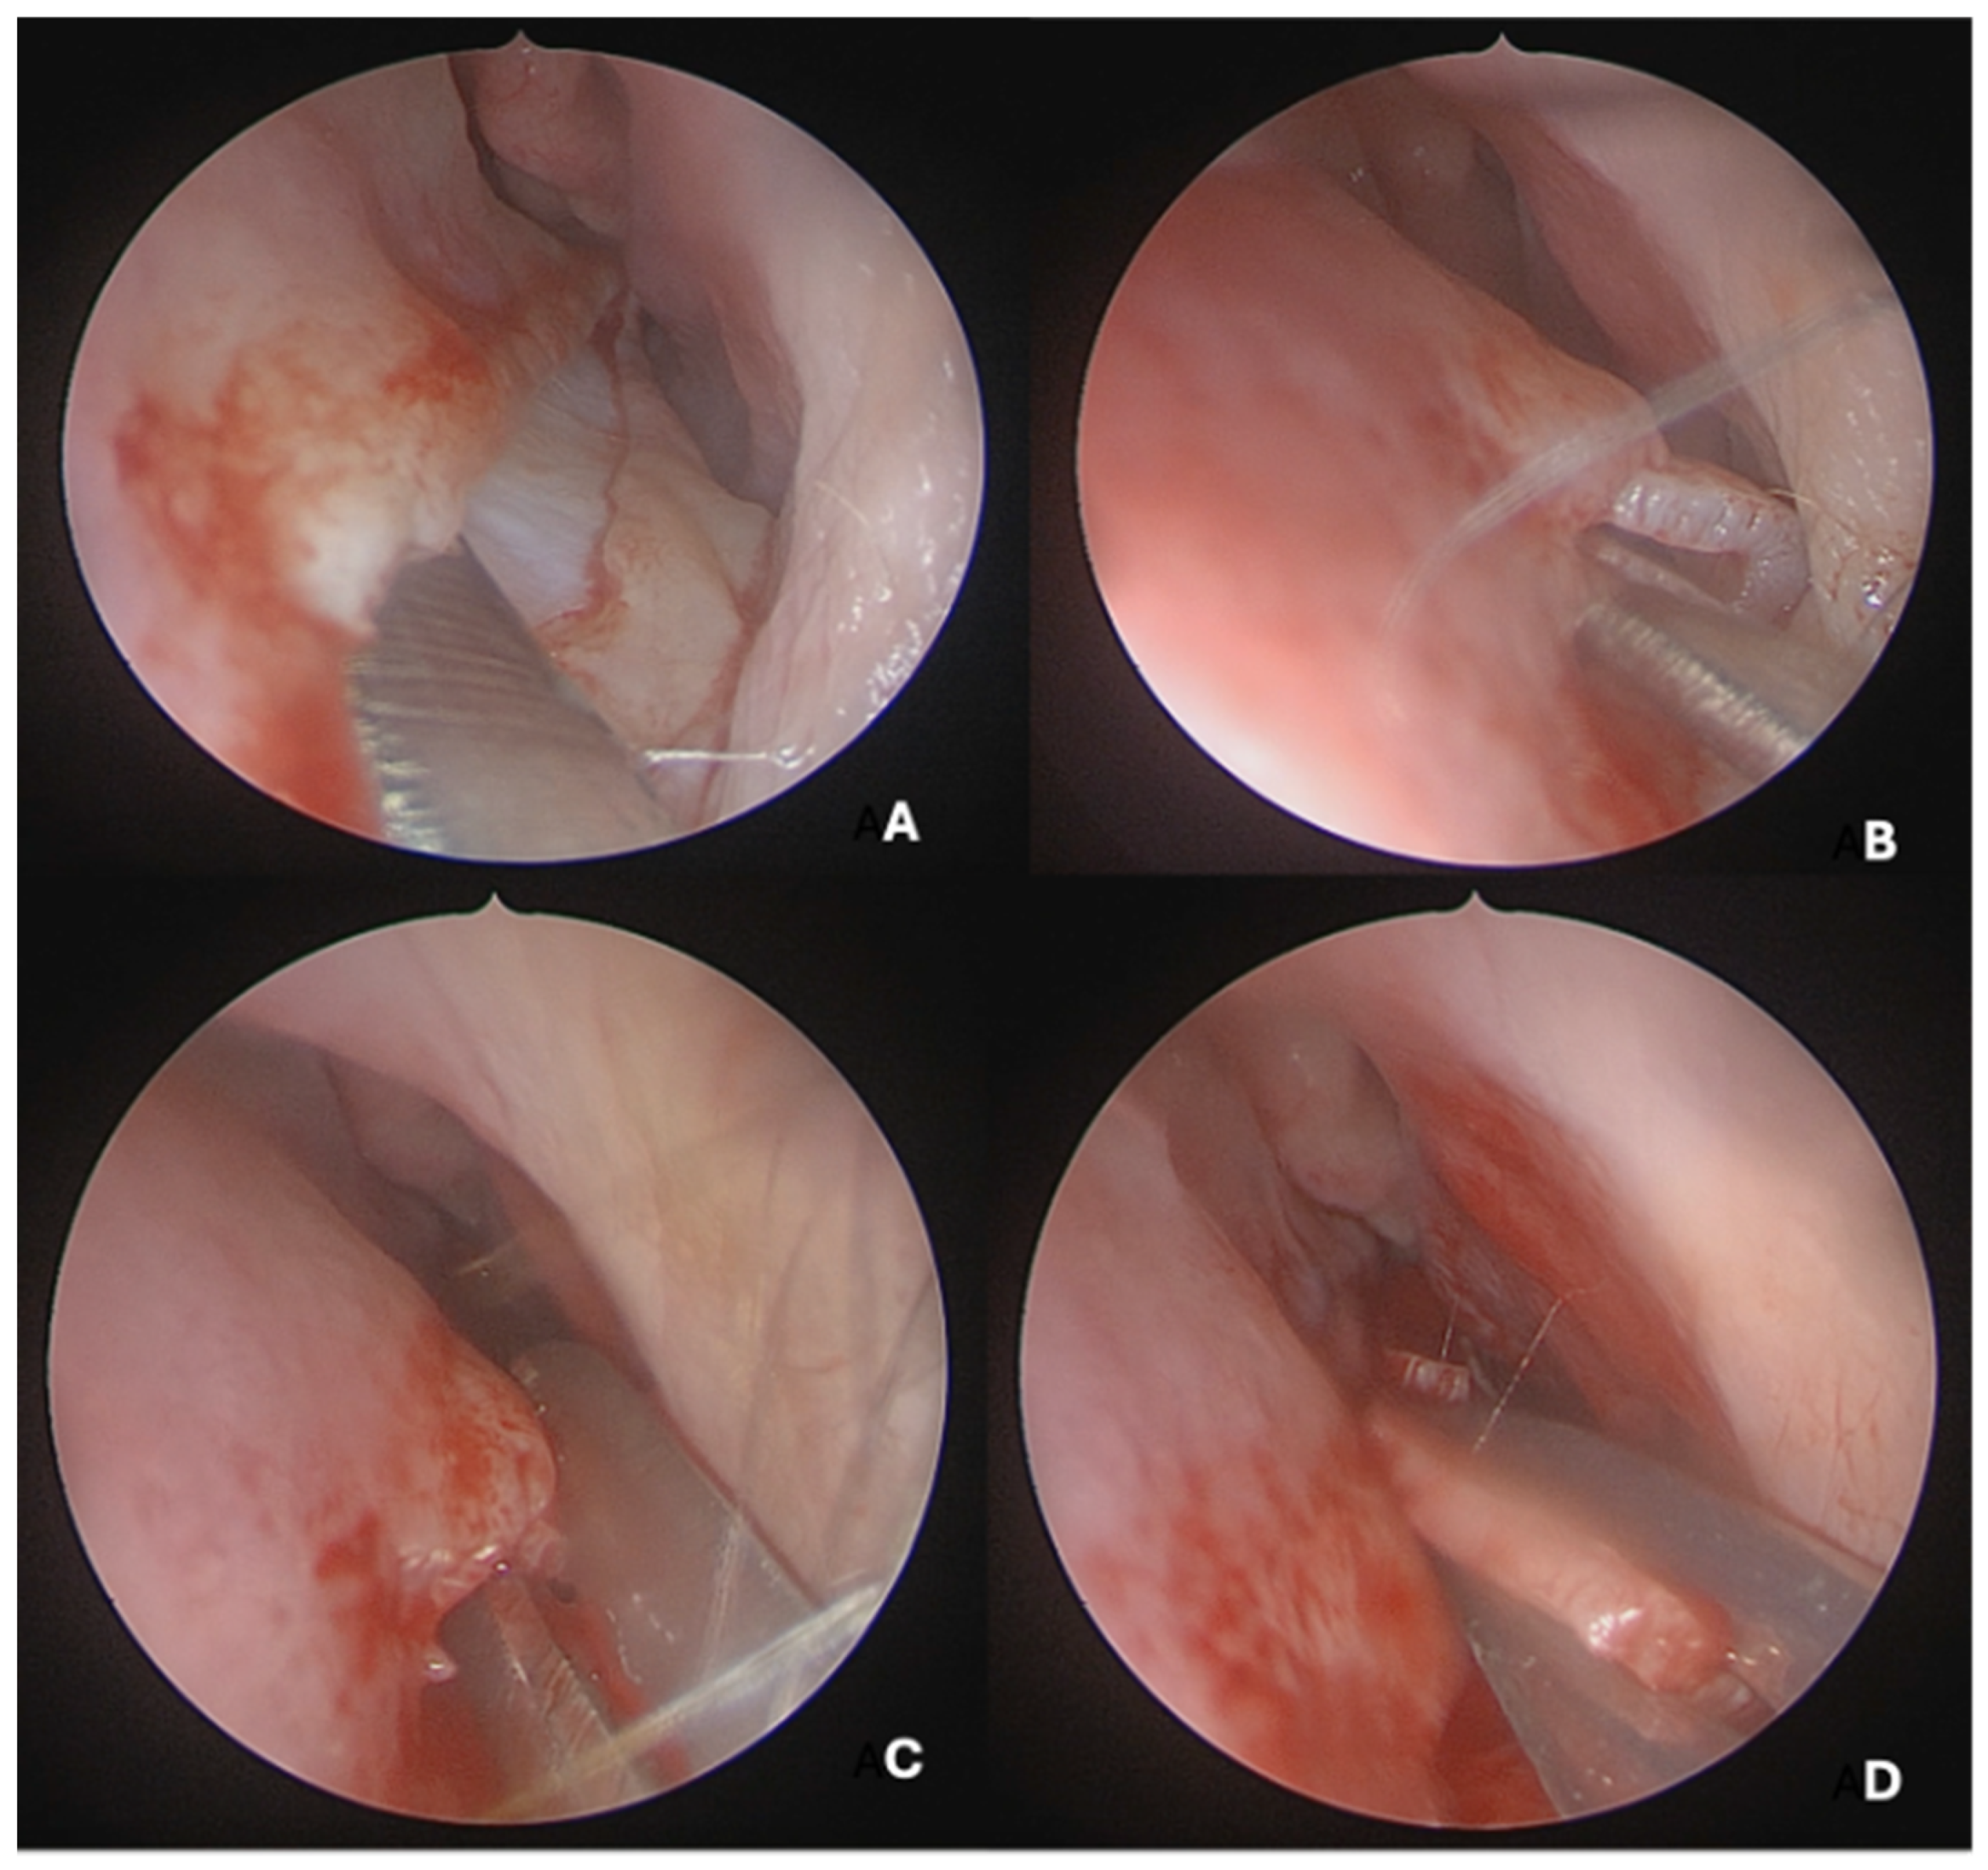

Under endoscopic visualization using a 0° endoscope, the following procedural steps were performed: For most septal deviations, standard Killian or hemitransfixion incisions were utilized (Figure 2). For Mladina types 5 and 6 deformities (corresponding to Cottle’s areas IV and V), a horizontal hemitransfixion incision was placed parallel to the nasal floor at the apex of the septal spur to adequately expose the most deviated segment, ref. [14] whereas more posterior or isolated deformities required a more posterior incision. Following the mucosal incision, mucoperichondrial flaps were elevated with a Cottle elevator, ref. [8] with optimal visualization assisted by a suction Freer elevator. Care was taken when elevating the mucosa over spurs to prevent tears due to thinning [8].

A full-thickness vertical incision was made through the cartilage a few millimeters anterior to the point of maximal deviation, which is typically located at the junction of the quadrangular cartilage and the perpendicular plate of the ethmoid [5]. The contralateral mucoperichondrial flap is then elevated in a similar manner. Once the cartilage and bone were separated from the mucosa, the deviated segments were excised using endoscopic instruments including forceps, Brünings punches, and scissors. The deviated portions of cartilage and bone were excised sharply, and the flaps are subsequently dissected inferiorly down to the nasal floor to correct deflections of the vomer. An osteotome was then positioned at the base of the spur to excise the bony protrusion (Figure 3). Deviated bony segments from the vomer or perpendicular plate of the ethmoid were removed as needed (Figure 4). After complete removal of the spur, the mucoperichondrial flaps were restored to their native positions [15]. When flap apposition was satisfactory, suturing was not required; in such cases, the incision line could be covered with a small segment of Gelfilm. Nasal packing and splints were employed only in selected cases [4].

Figure 2. (A) Horizontal hemitransfixion incision at the spur apex. (B) Flap elevation exposing spur. (C) Excising the deviated part of the nasal septum. (D) Cartilage resection preserving vomero-chondral junction.